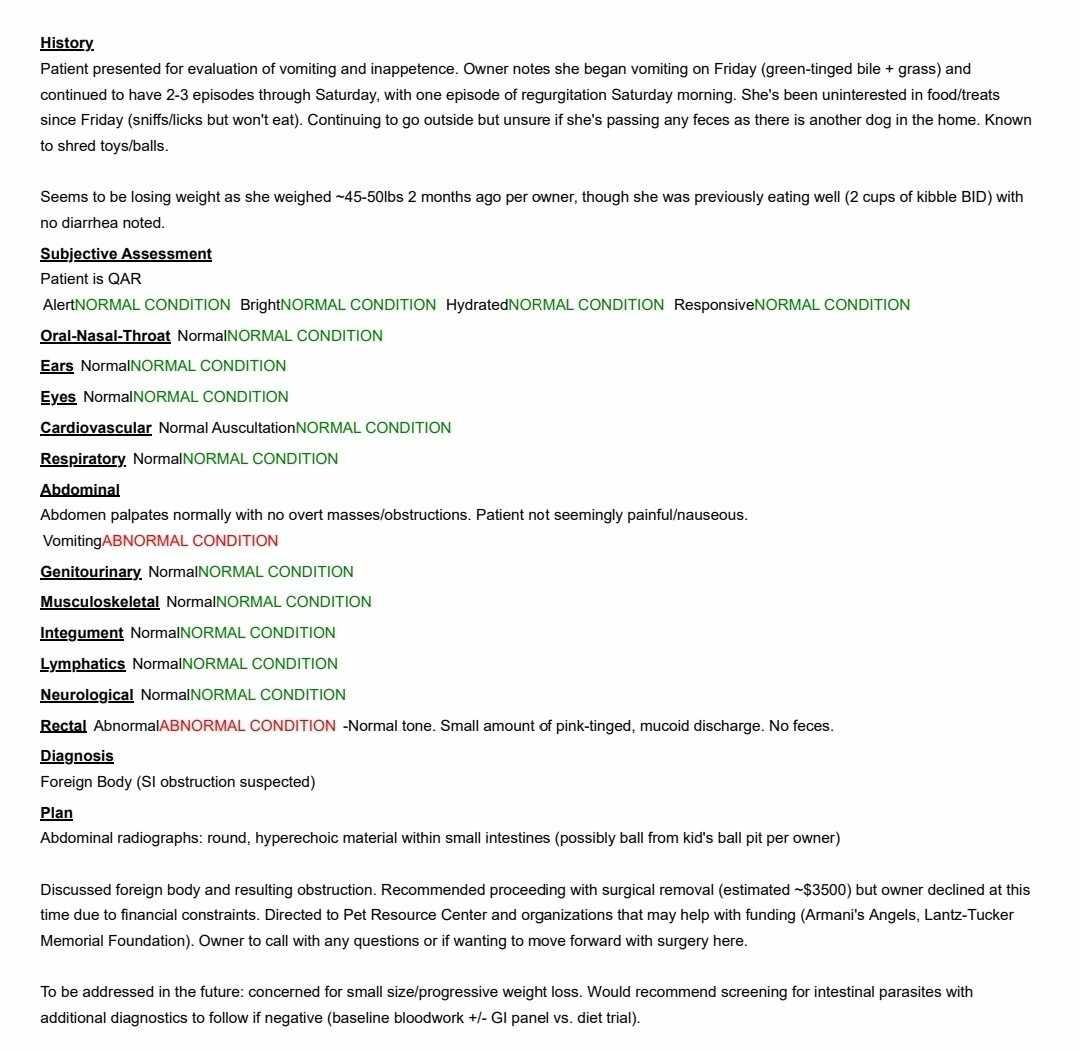

Hi everyone, my 3 year old husky appears to have a ball lodged into her large intestine obstructing her digestive tract. The vet said the surgery would cost 3500 and I do not have any funds to pay for it. I have no way to pay for any of the bill because this year has been one thing after another. I just payed 5k a couple months ago to start a custody case with my ex over our daughter, I had to spend another 5k to get my vans transmission replaced last month and that's right after I had just spent 3k on my van to get it tagged and legal. I just had to pay 500 last week to get my paternity test scheduled for my custody case. It's been one thing after another and I have nothing else and I really don't want to add loosing my dog to that list also.